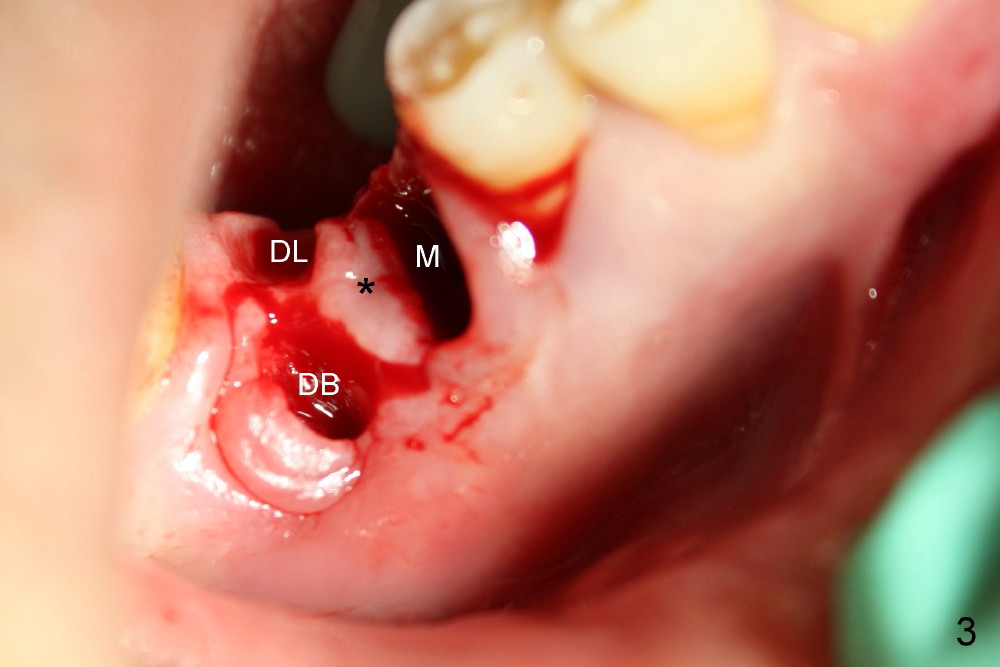

A series of osteotomes (Bone Scalpel, Bone Blade, and Round Tapered, Tatum Surgical) are used to displace the septum and furcal gingiva (* in Fig.4; O: 5 mm RT).

Drills are used to change osteotomy created by osteotomes more buccally. Taps are also applied. When 5x17 tapered implant (Fig.5 I) is inserted with torque >60 Ncm, the furcal gingiva (*) is further advanced distally to close DB socket (Fig.5 >) and DL one (Fig.6 <).